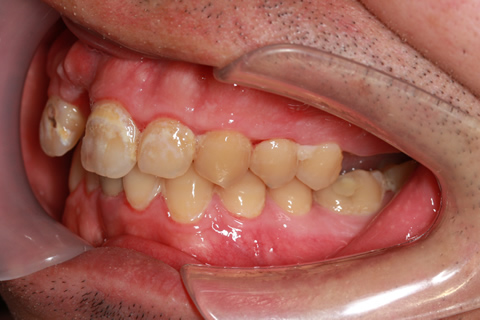

症例3

- 年齢・性別

- 60歳男性

- 治療期間

- 2ヶ月

- 抜歯

- なし

- 治療費

- 66万円

- 備考

- 右下6.7欠損

- 治療内容

- 右下6.7欠損部にインプラント埋入

- 施術の副作用(リスク)

- オペによる知覚障害。インプラントによる歯肉炎。インプラント脱落。